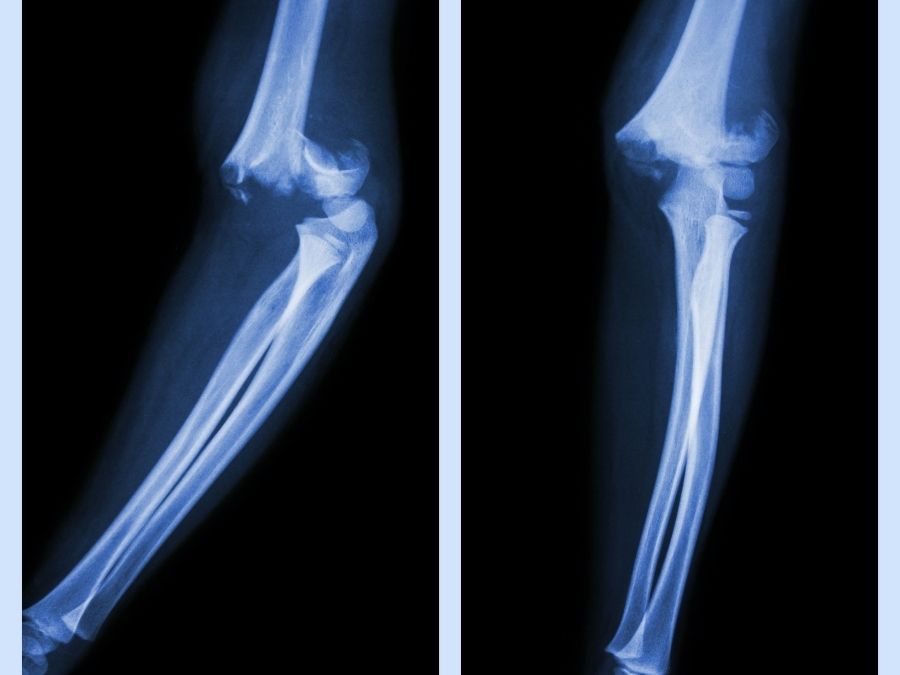

Tıp literatüründe Olekranon dirsek büküldüğünde arka kısmında görülen kemik çıkıntısıdır. Oldukça korunmasız olan bu kemikte çeşitli nedenler ile kırıklar meydana gelmektedir. Özellikle de bükülmüş dirseğin üstüne düşme, trafik kazaları ya da şiddetli darbe alma sonucunda Olecranon kırığı yaşanabilmektedir.

Aslında çok sayıda farklı dirsek kırıkları olmakla beraber, olekranon kırığı dışında humerus alt uç ve radius başı kırıkları en sık kırıklardır. Bazı radius başı kırıkları hariç bu kırıkların hemen hepsi cerrahi tedavi gerektirmektedir.

Dirsek kırığı; basit ve çok parçalı olabilmektedir. Dirsek kırığı belirtileri ise aşağıdaki şekilde sıralanabilmektedir;

- Şiddetli ani ağrı

- Şişlik

- Morluk

- Temas ile hassasiyet

- Parmaklarda uyuşma hissi

- Hareket ettirilememe

- Dirseği tam olarak düzleştirememe